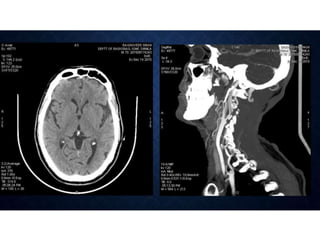

ACUTE STROKE IMAGINGPROTOCOL • When acute stroke patients present within 6 hours of the onset of symptoms - un-enhanced CT or with conventional/MR imaging. • Hemorrhage at unenhanced CT or >1/3 MCA territory - not treated with thrombolytic drugs. • Ischemia of < 1/3 MCA territory, those who present <3 hours after the onset of acute stroke - intravenous thrombolytic drugs • 3–6 hours after the onset of symptoms - CT angiography and CT perfusion imaging to assess the intracranial and neck vessels and detect any penumbra. • Intraarterial therapy is usually considered for patients in whom a penumbra is seen. • Patients in whom no penumbra is seen are not usually treated with thrombolytic drugs

CTP IN STROKE •• Stroke is a leading cause of mortality and morbidity in the developed world. • • The goals of an imaging evaluation are • I. to establish a diagnosis as early as possible • II. to obtain accurate information about the intracranial vasculature • III. to identify critically ischemic or irreversibly infarcted tissue (“core”) and to identify severely ischemic but potentially salvageable tissue (“penumbra”). • This information can guide triage and management in acute stroke.